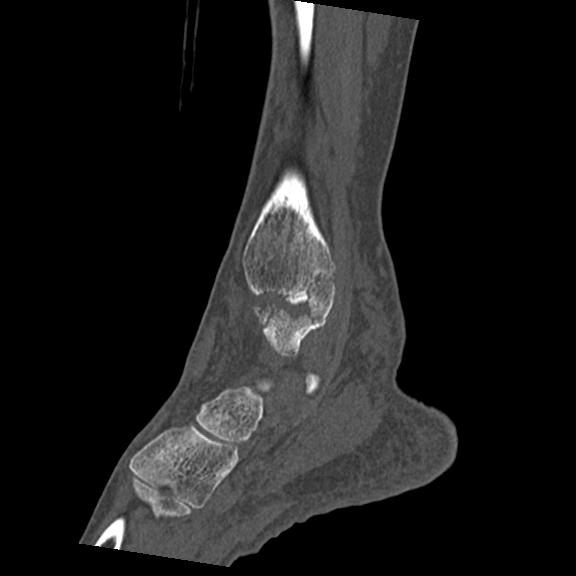

102755 1/4 2R 1/15 2R 右足関節 68歳女性 右三果脱臼骨折